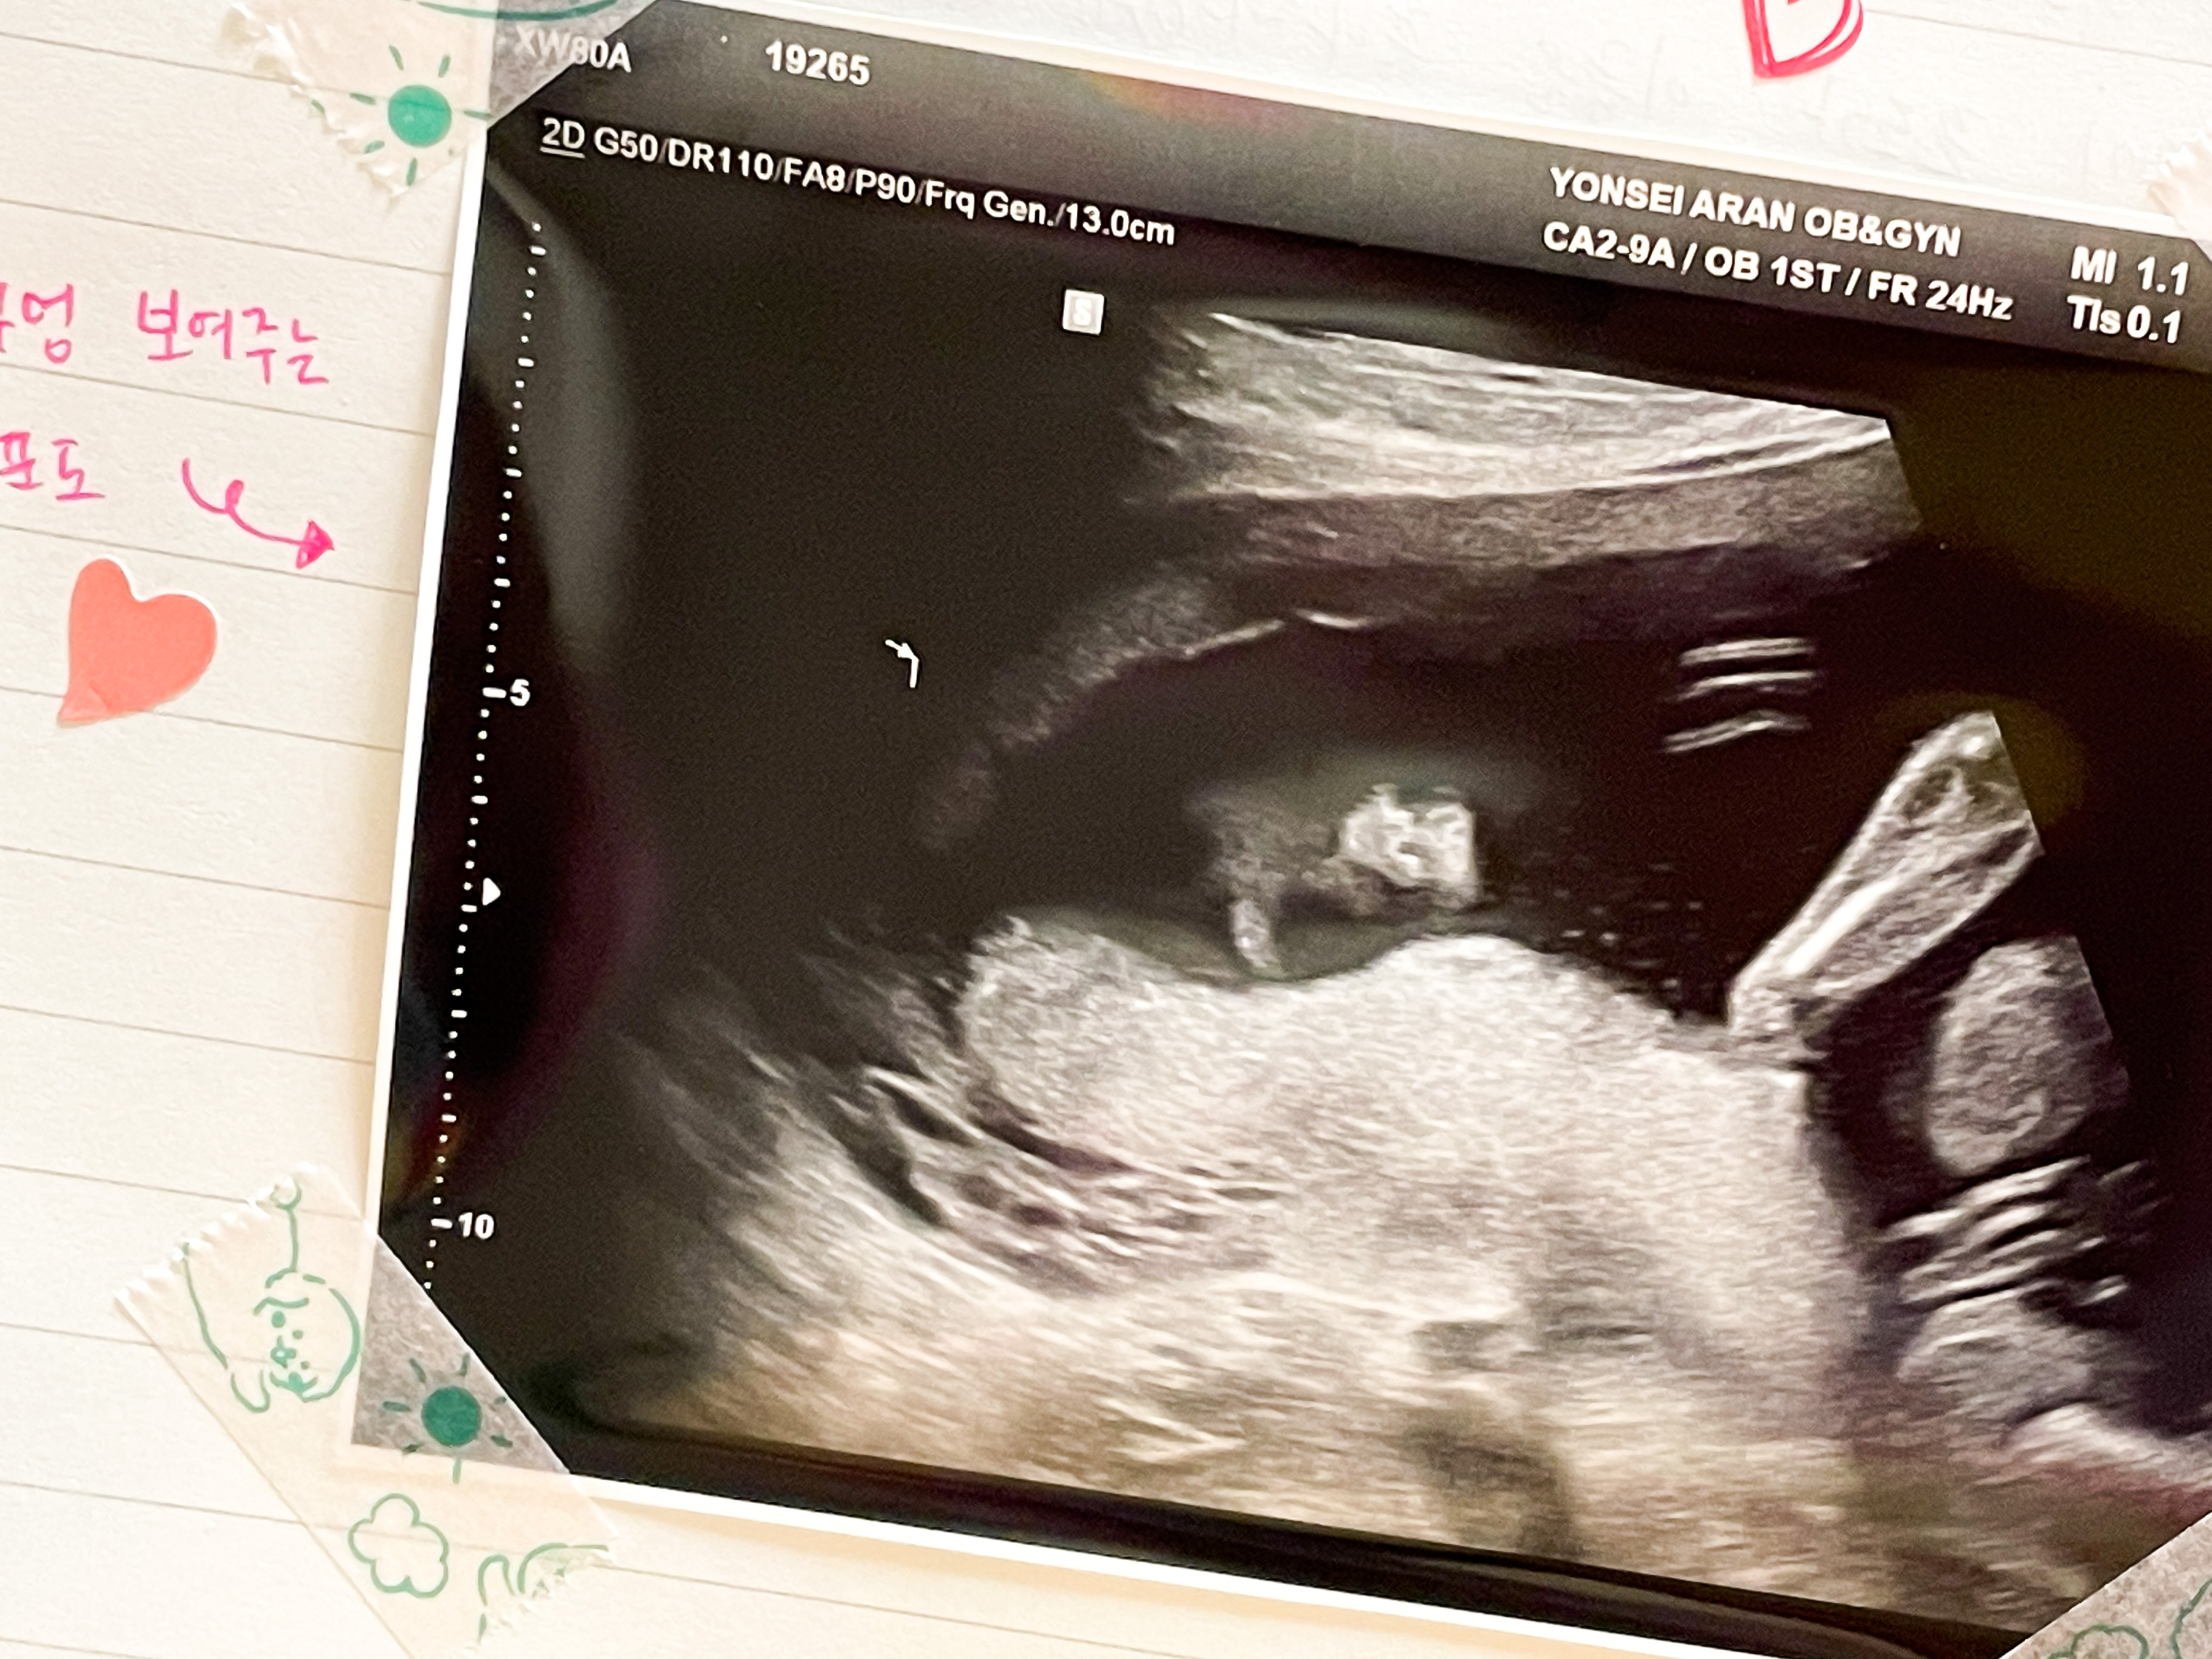

18주 5일 초음파 사진

정기 검진 받으러 병원에 갔다.

콧구멍이 보인다며 콧구멍을 찍어주셨다.

아니 왜이렇게 불편하게 있는건지....??